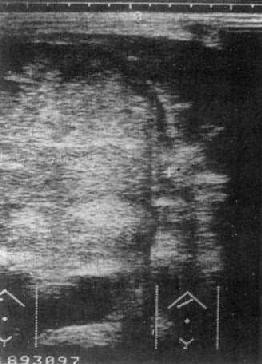

原发性肝癌:USG是影像学诊断中的首选方法。声像图上肝癌表现为聚集成团的强回声区,光团强弱分布不均,边比缘不规则。光点常粗糙明亮,与正常肝组织有明显差别。肿瘤区下方的正常肝组织回声强度降低,系因肝癌引起的超声衰减所致(图4-3-2)。

图4-3-2 肝癌(巨块型)

另一种表现是病变区以低声为主,该区光点稀疏。肿瘤区后方边缘无增强效应,可与囊肿鉴别。在弥漫型肝癌可见到弥漫分布的点片状、粗细不规则光点或光斑,诊断较难。